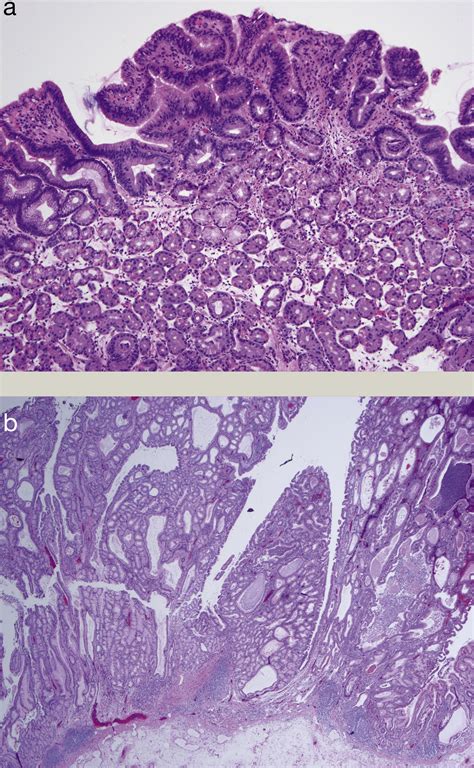

Serrated Polyposis Syndrome, formerly known as hyperplastic polyposis syndrome, is defined by the presence of a specific number and distribution of serrated polyps within the large intestine. These polyps are called “serrated” because of their distinct saw-tooth appearance when viewed under a microscope. While these growths are typically benign at first, their presence in large numbers suggests a genetic or environmental predisposition that may lead to cellular mutations over time.